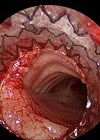

Endoscopic airway interventions in children

Open surgery for paediatric airway pathologies such as subglottic stenosis was hailed as revolutionary when many of today’s paediatric ORL specialists were in training. Equipment, facilities and training has moved on and the high-quality optics in modern endoscopes, coupled with...